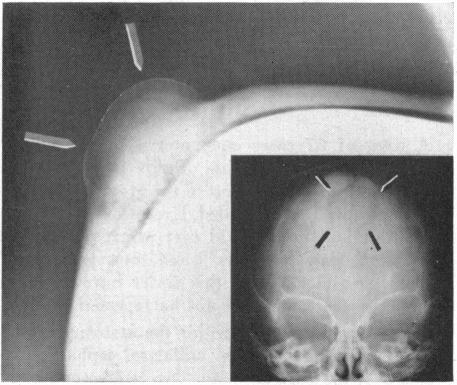

A clinico-pathologic recapitulation of experiences with a variety of masses which are visible and palpable and involve the cranium has led to the realization that examples of almost every major category of disease may be encountered. A review of the many varieties broadens our perspective of the diagnostic possibilities when confronted with a new case. The apparently innocent nature of scalp masses may be misleading, and this review can assist in alerting us to the need for stepwise investigation in tracking down the extent of involvement, especially intracranially. The use of limited office surgical procedures should be reserved for the simplest sebaceous cysts and other, readily identifiable, masses entirely limited to the scalp. The midline mass, in particular, deserves respect for its possible continuity with meninges or neural tissue. It should be remembered that the cranial mass may also be a manifestation of more widespread disease processes.